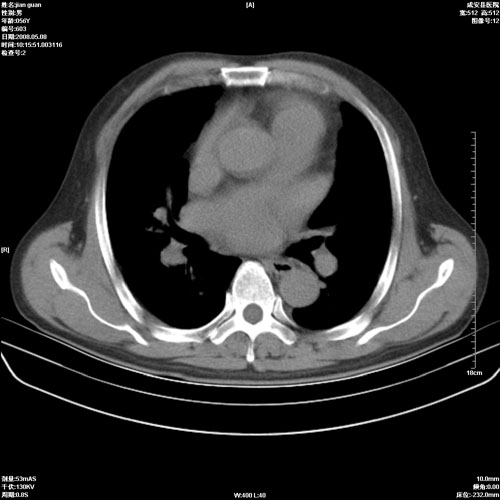

病人 男 60岁 主诉 胸闷 无明显发热 一般情况尚可。

考虑1心功不全,肺水肿

2.心脏增大(以左心室增大为著),请结合b超及听诊.

2.肺门血管扩张,心脏增大,为肺心病

3.肺心病.

陈旧性肺结核,左心房扩大,左心衰竭